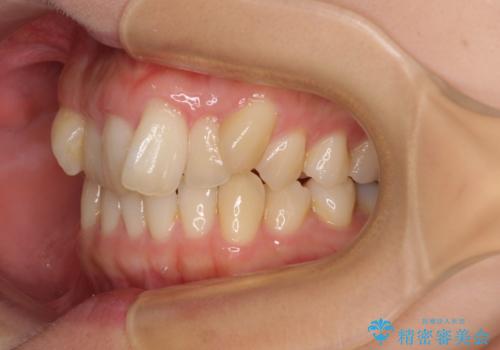

- 20代女性

- 目立つ八重歯を気にして来院された患者様です。

下顎歯列の叢生は軽度であることと、口元の突出感が全くなかったことから、八重歯解消のために上顎左右第一小臼歯を抜歯し、ワイヤー装置にて矯正治療を行うこととしました。